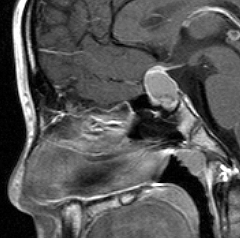

ちょっと小さな頭蓋咽頭腫です

トルコ鞍の中から発生する頭蓋咽頭腫は,身長の伸びが悪い(低身長)とかおしっこの量が多くて水をたくさん飲む(尿崩症)とかで発症します。それから視力の障害。たいていの場合は小さい腫瘍が多くて,鼻孔からの経蝶形骨洞手術で摘出できます。のう胞の部分(右のMRIの真っ白な部分)をつぶすだけの手術だと再発しますから,腫瘍を全部取る手術を目指します。そうしないと何度も手術を繰り返すか,放射線治療をすることになってしまいます。目標は下垂体の機能を少しでも残すことですが,下垂体正常組織との剥離が難しいことも多いです。幼児で副鼻腔(蝶形骨洞)の発達がなくても,ドリルで蝶形骨を削ればこの手術は可能です。でもそれができる外科医は少ないかも。この例は黄色肉芽腫との鑑別が難しいものでした。